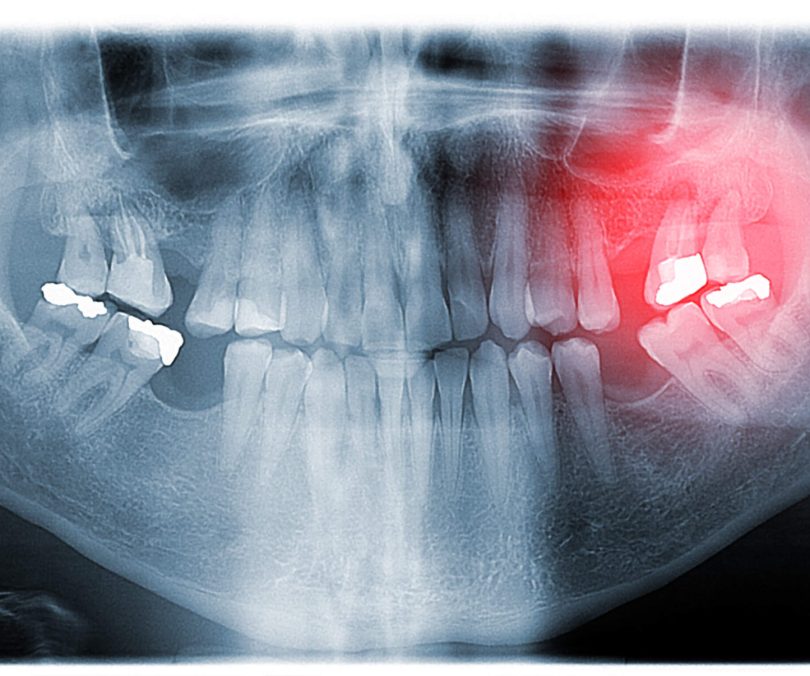

Impacted Wisdom Teeth: What’s Happening, What It Means, and When to Seek Advice

Wisdom teeth tend to cause uncertainty rather than sudden drama. For many patients, the discomfort starts quietly: a dull ache, a bit of…